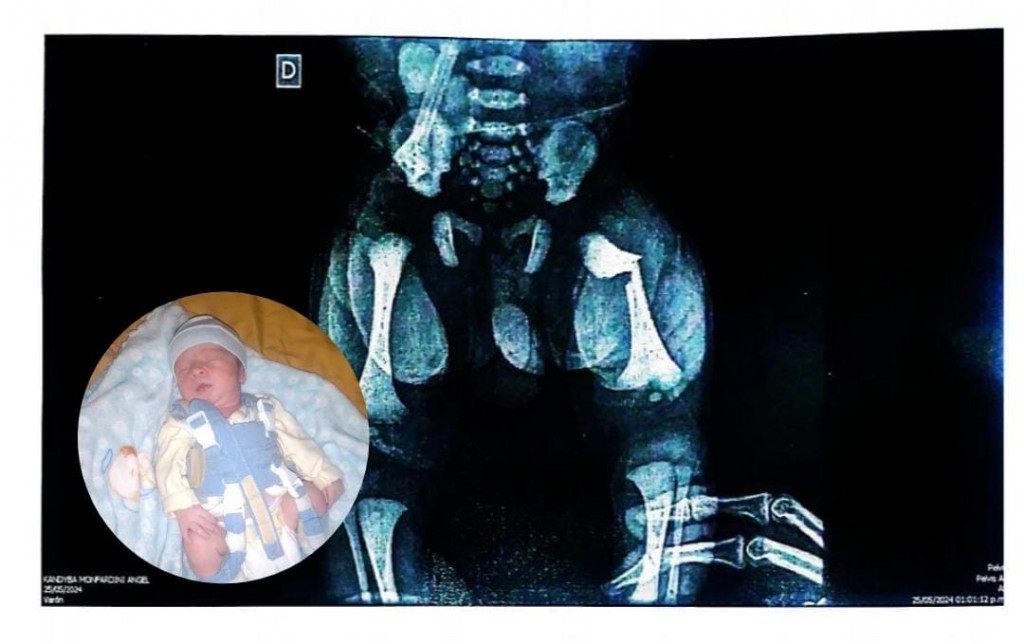

Yamila Monfardini se comunicó vía telefónica con Radio Manantial para realizar una denuncia pública contra el Sanatorio Parque y doctoras de esa institución. "Porque el 25 de mayo nació mi hijo y mediante una mala maniobra la doctora Luisa Pérez García le quedó el fémur izquierdo a mi bebé".

El 26 de mayo "me pasaron a mí y a mi bebé al hospital como que lo tuve ahí a mi bebé y ahí tramitaron una ambulancia particular para trasladarnos a Resistencia al pediátrico donde lo atendió el traumatólogo. A mi bebé le pusieron yeso 10 días, luego un arnés por 37 días más" añadió Yamila.